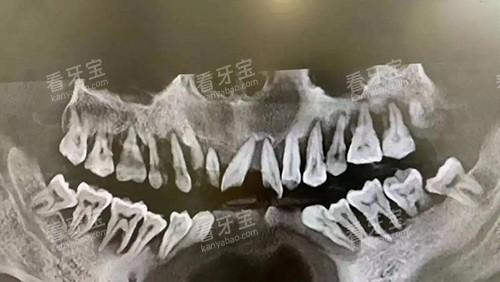

检查准备:可能需要拍摄X线片或CT辅助诊断